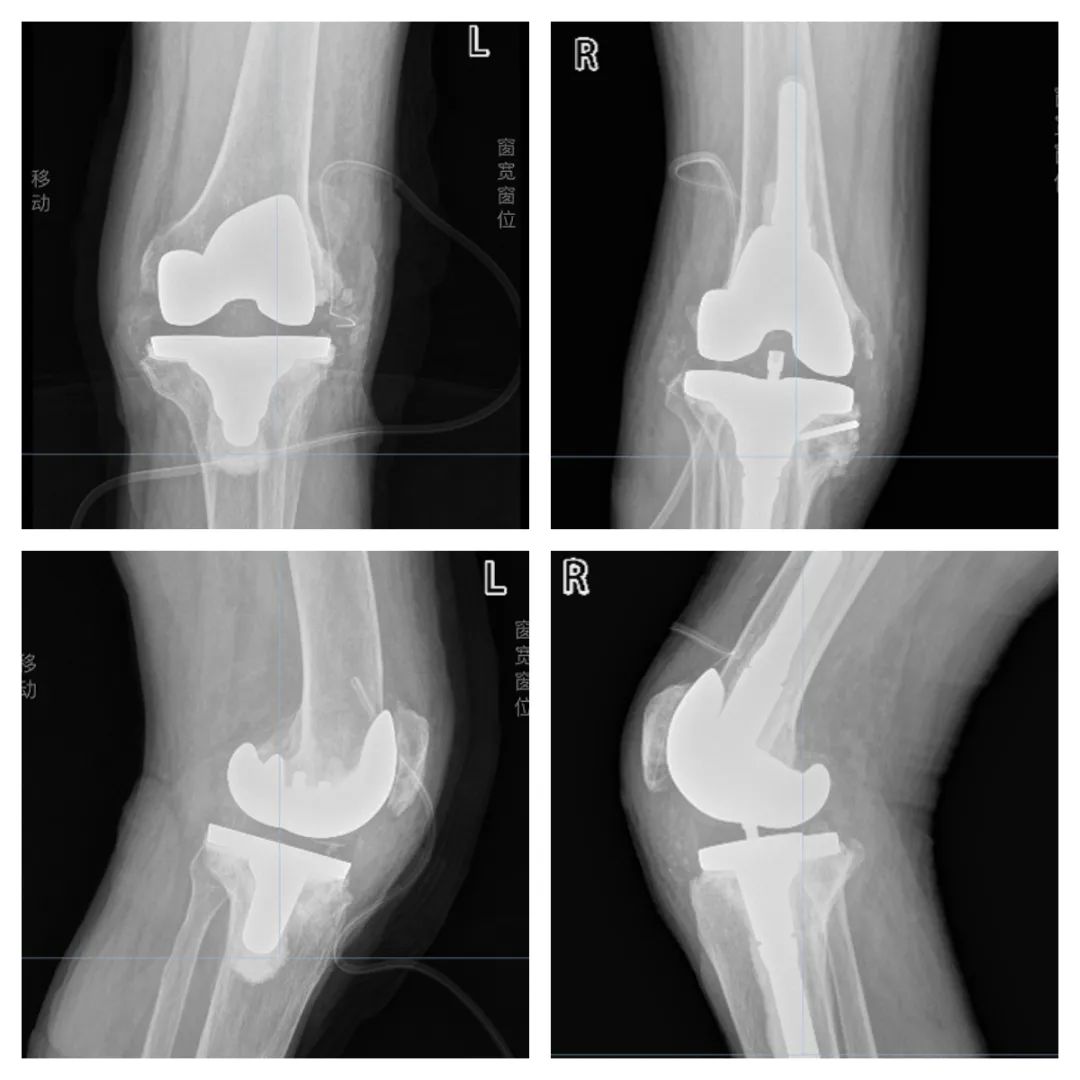

术后一周左右,陈大哥已经可以借助助步器下地行走了,通过精准的人工关节置手术,实现了 缓解关节疼痛、纠正关节畸形、改善关节功能 的目的,让陈大哥又“站起来”了!截止到目前,陈大哥的 膝关节可以正常屈伸,活动度良好,可以自行走路,疼痛症状消失、 关节功能较术前有了明显的改善。

双侧膝关节术后X 线片报告